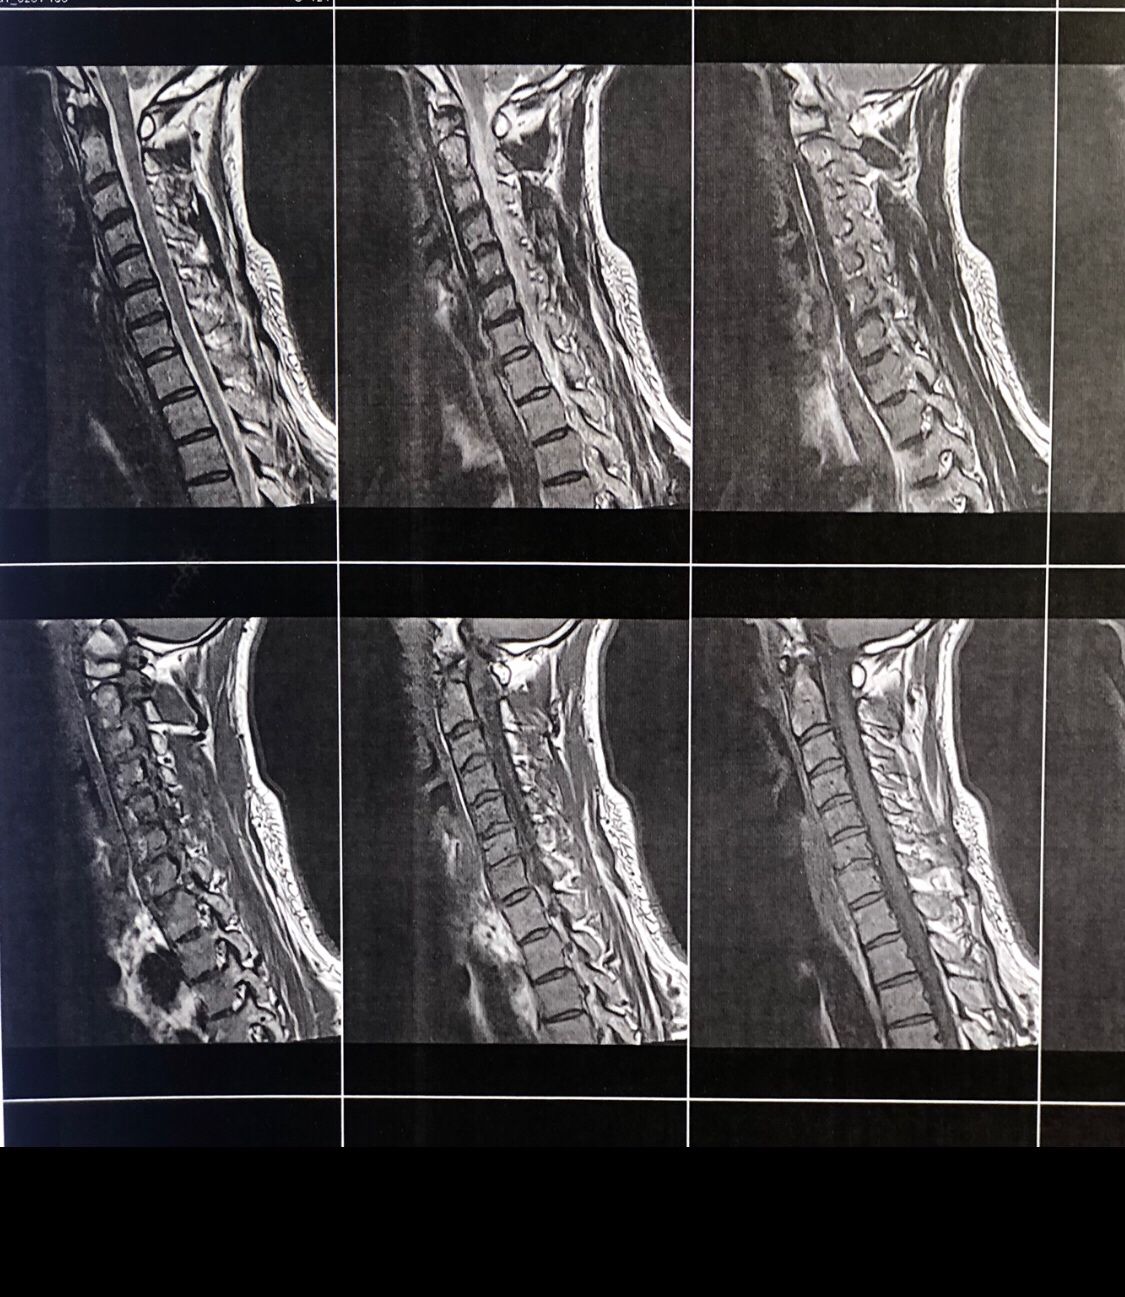

A 65-year-old patient presented to my office 20 days ago with right hip/gluteal pain, mainly occurring after walking approximately 200 meters. He also reported right shoulder and neck pain.

On examination, the right shoulder range of motion was normal. However, cervical spine (C/S) range of motion was severely restricted by about 80% in all directions. There was severe right C5–C7 dysfunction. Neurological examination revealed a positive right-sided Hoffman’s sign, unremarkable Babinski sign, and bilateral L4 deep tendon reflexes graded 1+. On palpation of the lumbar spine, step defects were noted. Right hip examination was otherwise normal.

Cervical and lumbar MRI, dynamic lumbosacral X-rays, and EMG/NCV of the lower limbs were ordered. The patient brought all results today (August 18, 2025).

Request:

Please review his MRI and X-ray findings. Based on these, what are your differential diagnoses, final diagnosis, and plan of management (POM)?